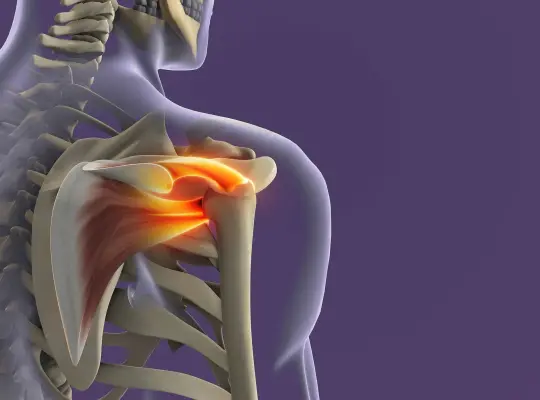

Operacje barku to jedne z najczęściej wykonywanych zabiegów w Oddziale Ortopedycznym Szpitala SALUS, a dzięki temu także wizytówka i potwierdzenie wysokiej klasy operatorów ze specjalistą ortopedą Krzysztofem Mazurem na czele.

Artroskopie operacyjne barku z wszczepem i bez wszczepu implantów, plastyka niestabilności, rekonstrukcje stożka rotatorów, zespolenie złamań to tylko część z obszernej listy wykonywanych operacji.